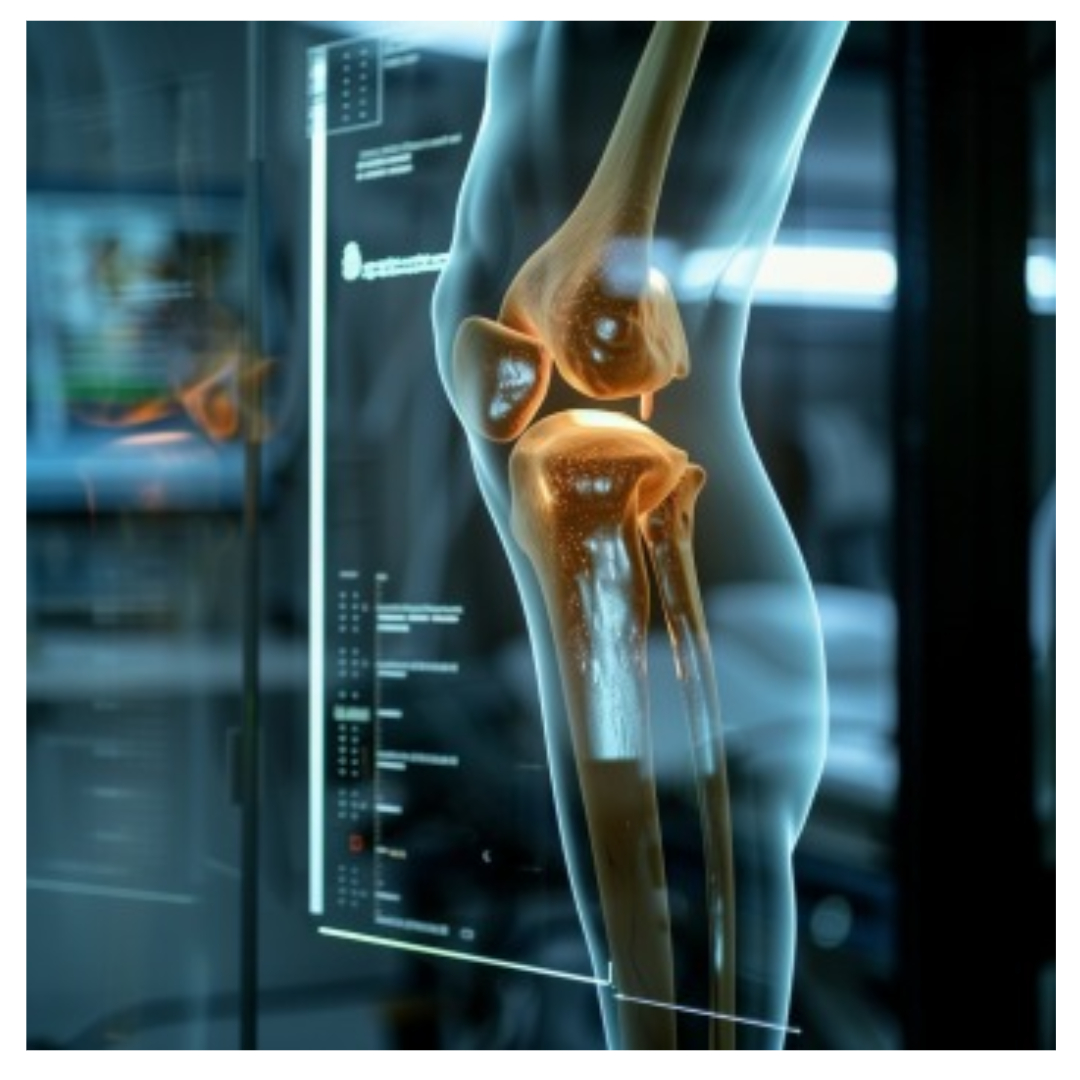

관절염은 어깨 관절에도 발생할 수 있습니다. 특히 퇴행성 관절염은 나이가 들수록 어깨 관절의 연골이 닳으면서 발생할 수 있는데, 이로 인해 통증과 함께 어깨의 움직임이 제한되기도 합니다.